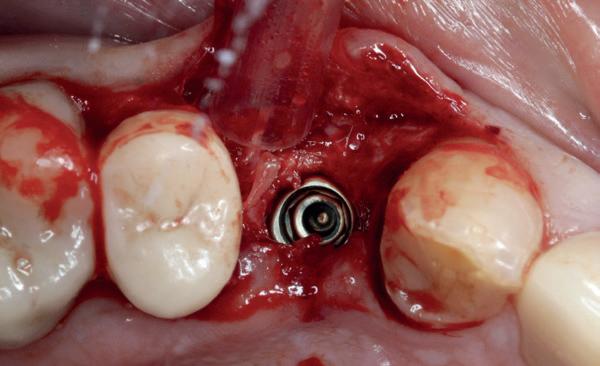

Het kantelpunt: de patiënt komt terug (afbeelding 14-16)

De patiënt meldde zich opnieuw in de praktijk met klachten: pijn, zwelling en een duidelijke intraorale infectie. Bij inspectie zag ik direct een probleemhet ging om een klassiek beeld van peri-implantair botverlies met een abces. Dit patroon van botverlies en infectie spiegelde sterk de gevolgen van thermische trauma.

Op de röntgenfoto’s zag ik wat ik al vreesde: er was botresorptie rond het implantaat. De zachte weefsels waren ontstoken en het implantaat vertoonde teke-

nen van mobiliteit. Op dat moment wist ik precies wat er was misgegaan.

Dit was geen kwestie van een verkeerde occlusie of een slecht gekozen abutment. Dit was een puur biologisch probleem, veroorzaakt door mijn onderpreparatie van de osteotomie en de daarmee gepaard gaande botnecrose of compressie. Mijn streven naar immediaat belasten had me verblind, en ik had een fundamentele regel van de implantologie genegeerd: bot moet kunnen ademen. Op dat moment had ik geen andere keuze dan de situatie te herstellen.